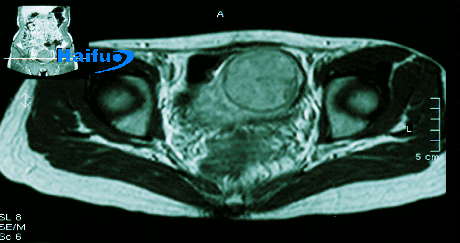

超声消融治疗前超声造影:肌瘤血供丰富

治疗前